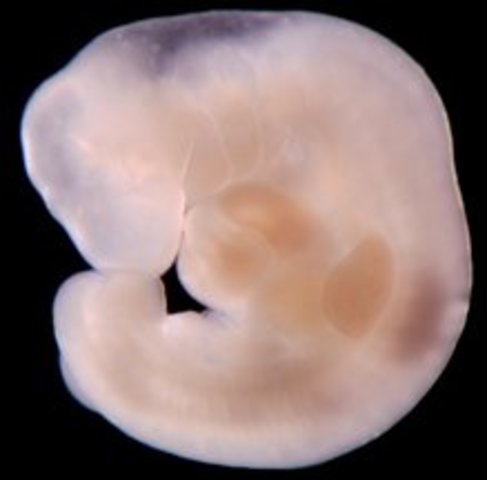

• week 5 Begginning of Embryonic stage

week 5 Begginning of Embryonic stage

cells of the ovum start making the amniotic sac, and placenta. other cells will begin to begin forming the embryo itself. embryo wil double in size by the end of the week. The embryo grows to 5mm

Fact: nerve and spinal chord begin early stages of development.